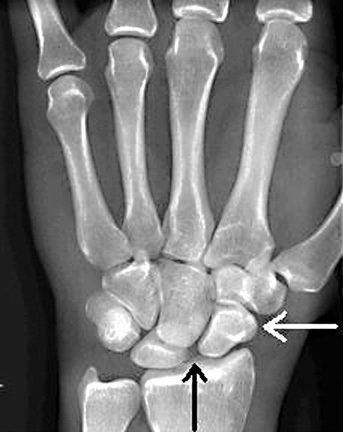

- Widening of the scapholunate joint space >3mm

- Rotary subluxation of the scaphoid

- PA view: Cortical ring sign (circular cortex of the bone is more prominent)